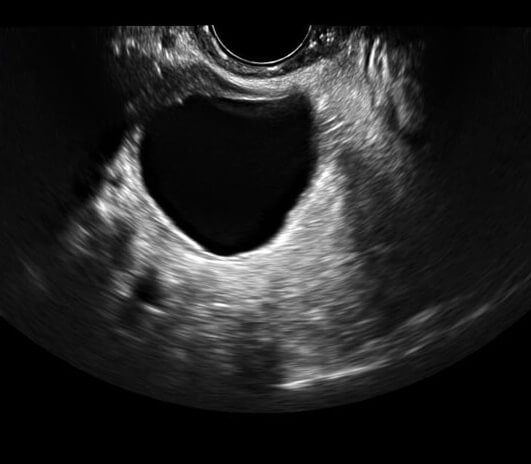

@TijanTijan87表示,去年,她的母亲一直抱怨肚子疼,月经周期不稳定。所以,她带着母亲去了附近的Klinik Kesihatan医院做超声波检查。医生们在她的肚子里发现了一个4-5cm的囊肿,之后她被转到了沙捞越总医院的妇科。

医生建议她先住院观察,说不定囊肿会自行消失。@TijanTijan87说:“但是我妈妈的情况并没有好转,囊肿一天比一天大,2019年7月,医生建议她接受手术切除囊肿。由于7月和8月的预约已满,我的母亲终于在9月进行了移除手术。手术前,我母亲看起来好像怀孕了。她的囊肿长约12厘米,重近4公斤!